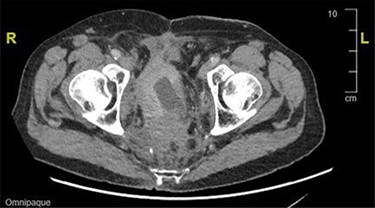

CT and magnetic resonance imaging (MRI) of the abdomen and pelvis indicated that a loop of small bowel was caught up in the pelvic mass resulting in a mechanical small bowel obstruction (Fig. 2).

CT image showing distended bowel loops indicating bowel obstruction caused by the pelvic mass.